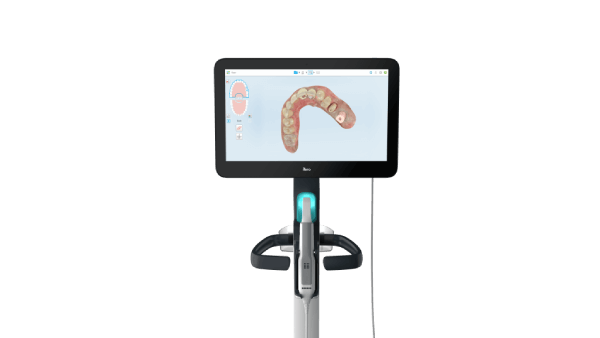

一系列不同的口腔数字印模仪。

通过爱齐口腔健康套件,您和您的团队可以通过单次扫描,为患者提供针对各种临床状况的个性化评估,既提高了接诊效率,又增添了交流互动。

iTero NIRI(近红外线成像技术),辅助检测邻面龋齿病变^

根据最近的一项研究,iTero Element 5D Plus口腔数字印模仪的iTero NIRI技术对后牙邻面龋的检测灵敏度为96%。#